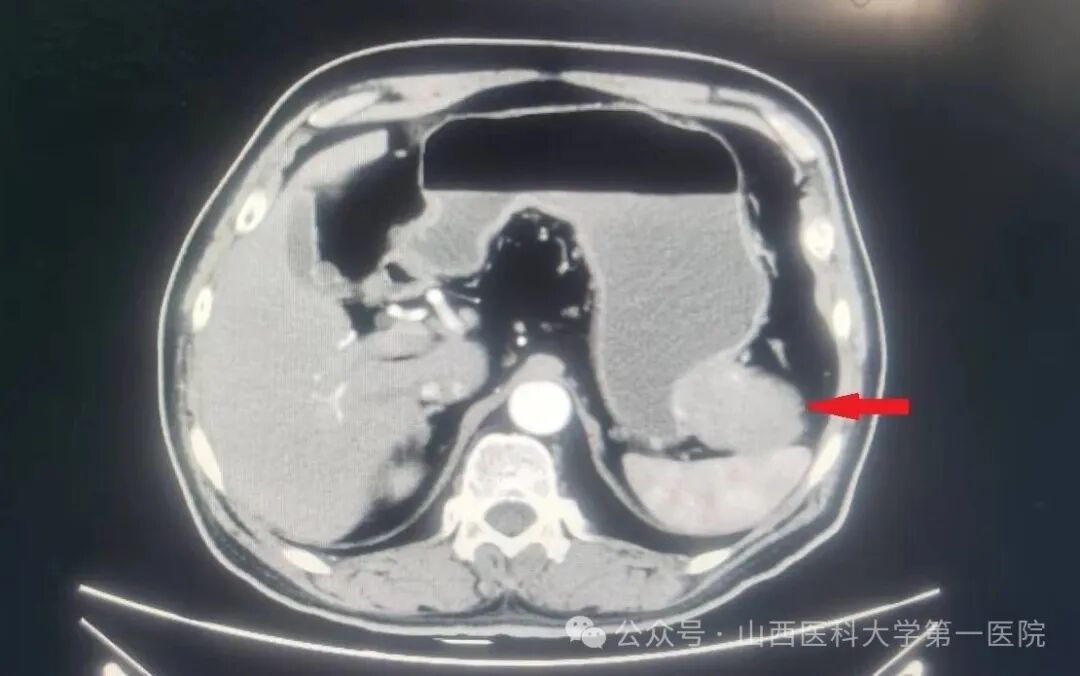

医生给王先生仔细解释了病情,安排了入院,完成了腹部增强CT,提示“胃大弯侧外生型肿物,考虑胃肠间质瘤”,与周围界限清晰。他顺利接受了腹腔镜微创手术,术后顺利恢复。